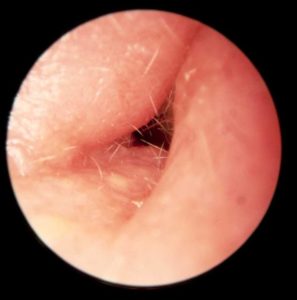

Bir uzman doktorla görüşmeniz ve doktorun görüşleri en önemli noktadır. Genellikle çıplak gözle görülmektedir. Doktora söyleyeceğiniz belirtiler ağrı, akıntı ve benzeri belirtiler teşhisin konulmasına yardımcı olacaktır. Doktorun otoskop adı verilen bir aletle kulak içine bakması ve iltihaplanmayı görmesi teşhisin daha doğru konulmasını sağlar. Kulaktan alınacak örnekler de laboratuvarda incelenerek otitis externa olduğu kesinleşir. Fakat örneklenmeye genellikle gereksinim olmamaktadır.